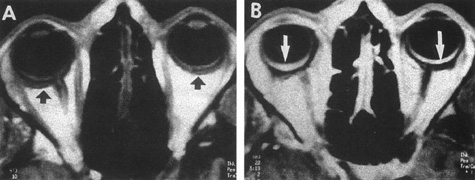

197. Ventura AC, Remonda L, Mojon DS: Intermittent visual loss and exophthalmos due to Blue rubber bleb nevus syndrome. Am J Ophthalmol 132:132, 2001

Back to Top